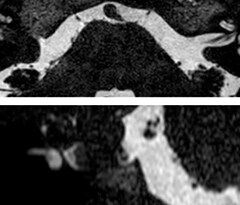

Ultimate precision at maximum speed with Dual AI

Take the leap forward with SmartSpeed Precise, the next generation acceleration technique that expands the proven Compressed SENSE and SmartSpeed technologies with a unique integrated Dual AI innovation, providing ultimate precision at maxiumum speed.

Read more

SmartSpeed Precise